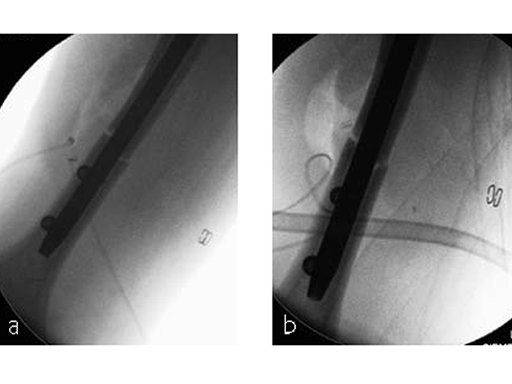

The patient was operated on in beach chair position. For the exploration of the radial nerve, a limited anterolateral approach was used. The nerve was mobilized and retracted laterally. An anterolateral approach to the proximal humerus was performed. The supraspinatus showed a small acute rupture without retraction. The supraspinatus tendon was split to get access to the insertion area on the humeral head. A 270 mm long MultiLock Humeral Nail of 8.5 mm diameter was inserted under visual and x-ray control to the desired endpoint. Reduction of both the proximal and the distal humerus fracture was anatomical. In the lateral view there was a small gap, and it was decided to apply compression after distal locking (Fig 4). Proximally, three MultiLoc screws were inserted and a 2 mm end cap was placed. Finally, the supraspinatus rupture was reconstructed with transosseous sutures and secured with an augmentation plate. The posterior greater tuberosity fracture was secured with Fiber Wire to the MultiLoc screws. Figure 5 illustrates the definitive fixation.

Postoperatively, no sling was used because the patient stayed in medically induced coma.